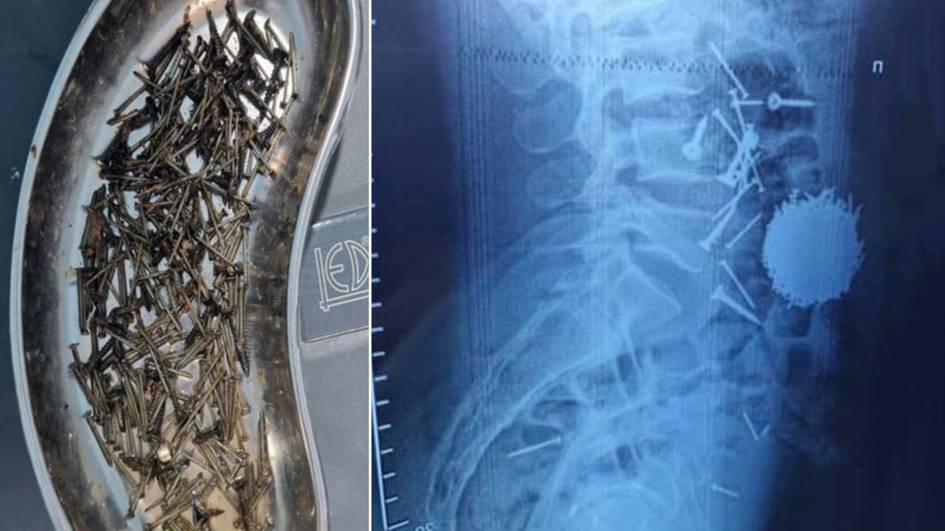

Самарқандда эркак стресс сабаб 200 грамм мих ютиб юборди